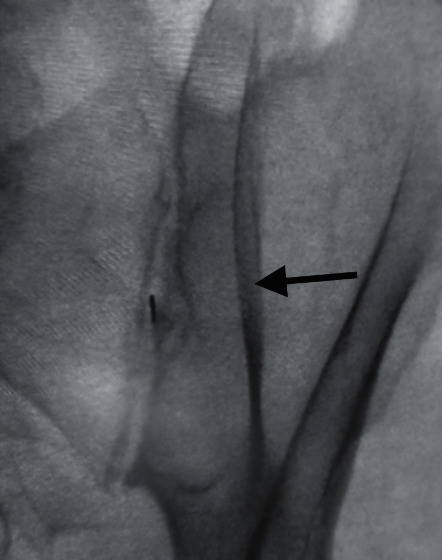

Arthrogram Interpretation:

• The joint capacity is typically 2.0 mL or less — inject only 0.1-0.2 mL of contrast initially

• Initial intra-articular flow will cap the inferior aspect of the lucent joint space and fill a slightly expanded inferior recess

• True intra-articular spread appears as a thin line (<1 mm) centered between the cortical joint margins

• Normal sacculations may extend peripherally from the joint space